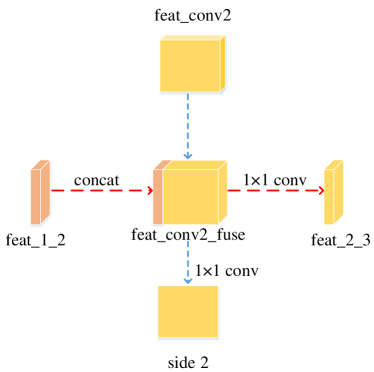

We adopted bottom-top short connections to deliver detail information just as shown in Figure 4. There are three bottom-top short connections in total. Suppose we use VGGNet as backbone. We can observe from Figure 4 that there are four groups of convolution (conv1, conv2, conv3 and conv4) for feature learning in total. We first convolved the last convolution of each group using 16 convolution kernels with size 11. Then, the obtained feature maps are up-sampled 1, 2, 4, 8 respectively to restore to original resolution. Bottom-top short connections are among feat_conv1, feat_conv2, feat_conv3, and feat_conv4.

Let’s take bottom-top short connection between feat_conv1 and feat_conv2 as an example (see Figure 5). The information (feat_1_2) passed from feat_conv1 is concatenated with feat_conv2 to get feat_conv2_fuse. Then, one hand hand, we perform a 11 convolution operation on feat_conv2_fuse to get the information (feat_2_3) delivered to feat_conv3. On the other hand, we performed convolution operation with a kernel size of 11 and sigmoid transformation for feat_conv2_fuse sequentially to obtain the segmentation result (side 2). At last, side 2 is compared with the ground truth to get the loss of the second side-output layer.